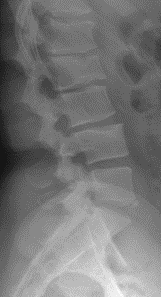

These findings include wedging of greater than 25% of L1 and L2, well-defined endplate concavities at L2 and L4, limbus bone at L5, and disc height narrowing at L1/2 and L2/3 (Figure 3 and 4). If these findings were noted in the thoracic spine, the diagnosis of Scheuermann’s disease would be fairly easy to assume; however, in the presence of a normal thoracic spine and localized abnormality of the lumbar spine, the diagnosis is more complicated.